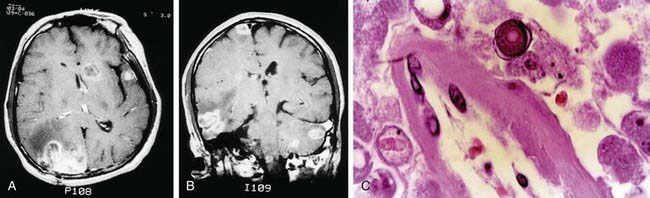

Granulomatous amebic meningoencephalitis may occur weeks to months after infection. The presenting signs and symptoms are often those of single or multiple central nervous system space-occupying lesions and include hemiparesis, personality changes, seizures, and drowsiness. Altered mental status is often a prominent symptom. Headache and fever occur only sporadically, but stiff neck is seen in a majority of cases. Palsies of the cranial nerves may be present. There is also 1 report of acute hydrocephalus and fever with Balamuthia. Results of neuroimaging studies of the brain usually demonstrate multiple low-density lesions resembling infarcts or enhancing lesions of granulomas (Fig. 272-1).

image

Figure 272-1 A and B, MRIs of the brain of a patient with Balamuthia mandrillaris granulomatous amebic encephalitis. Multiple enhancing lesions are seen in the right hemisphere, left cerebellum, midbrain, and brainstem. C, Photomicrograph of the brain lesion from the same patient showing perivascular amebic trophozoites. A round amebic cyst with a characteristic double wall is seen in the top center (hematoxylin and eosin, original magnification ×100).

(From Deol I, Robledo L, Meza A, et al: Encephalitis due to a free-living amoeba [Balamuthia mandrillaris]: case report with literature review, Surg Neurol 53:611–616, 2000.)